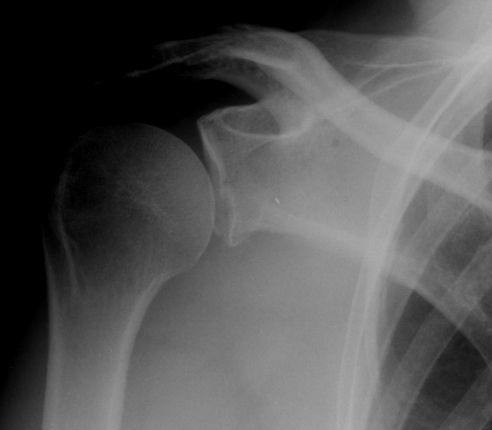

Case 1

Type I

Fractures of the Glenoid rim

I A anterior

I B posterior

Differentiate from small bony Bankart

- ORIF if > 1/4th or > 10 mm displaced (Neer)